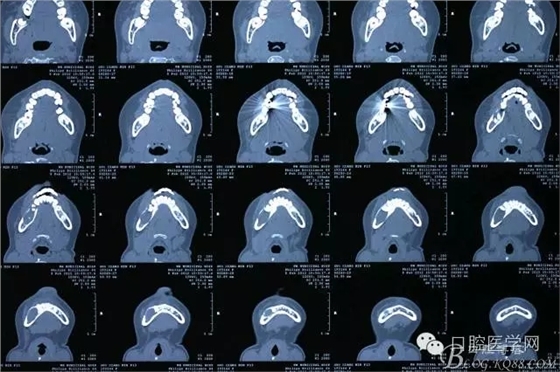

查:右側(cè)第二前磨牙第一乳磨牙恒尖牙頰側(cè)前庭溝隆起,捫有乒乓球感。曲斷及CT示:右側(cè)第二前磨牙第一乳磨牙恒尖牙根尖區(qū)有一囊腫,頰舌側(cè)骨板極薄,牙根無吸收,第二前磨牙牙根位于囊腫中,第一雙尖牙牙冠遠(yuǎn)中水平向阻生,牙冠位于囊腫中。經(jīng)協(xié)議:手術(shù)摘除創(chuàng)傷大,同意開創(chuàng)引流保守治療。